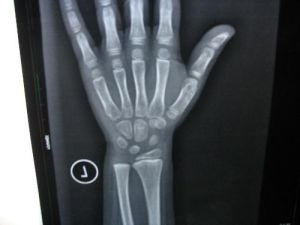

其中手腕骨發育圖譜(G—P圖譜)法廣為流傳。G-P圖譜是以美國中上層家庭的兒童為基礎,從出生到成年的縱向研究結果。圖譜法主要依據兒童青少年不同年齡手腕部骨化中心和乾骺的出現、消失順序,建立男女骨齡標準圖譜,評價時將待測X線片與圖譜逐個對照,取最相近者為其骨齡,若介於兩個相鄰年齡圖譜之間,則取均值來估算。此法簡便、直觀、易行,各國或地區相繼建立了各自的標準圖譜。評分法

圖譜法主觀性強、偏差大,且骨成熟率不清楚,因此科學家通過研究於1962提出TW1骨齡記分法,1975年修改為TW2法。該法取左手腕正位片20塊手腕骨,將各骨按不同發育等級分為8—9期,賦予不同分值,總骨發育分(SMS)從0—1000分。由手腕x片累計各骨發育分,然後查骨齡得分表或SMS一年齡曲線,求得骨齡。另外還有一些新方法可以藉助於現代科技手段評測骨齡,如:計算機輔助骨齡評估、超聲骨齡評測、套用雙能X線吸收測量儀(DXA)評測骨齡等。

骨齡的測定都是利用骨的X線攝片、根據骨發育的X線徵象即成熟標誌而測定的。19世紀末Boas首次提出生長速率的概念,在發現如何用X射線攝片後不久,人類生長學學者們很快將此概念和技術用於骨發育的研究,對骨齡的測定方法進行了長期探索和不斷改進。

骨齡的測定方法較多,可分為計量骨化中心的“骨齡計數法”、與標準圖譜比較的“骨齡圖譜法”、按骨發育分期評分的“骨齡評分法”三種類型,並正在向計算機輔助評定骨齡的方向發展。但是,通過比較國內、外檢測骨齡的各種方法後確定中國兒童骨齡評分法: